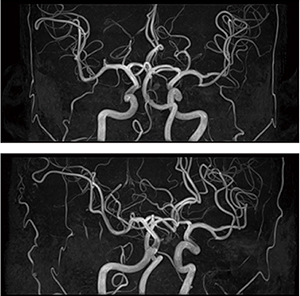

症例1:頭部MRA

症例2:頭部拡散強調画像(syngo RESOLVE)

「ルーチン検査では,体動補正のアプリケーションである“syngo BLADE”を使用していますが,アーチファクトのない精度の高い画像を撮像できています。また,顔面けいれんや動眼神経麻痺の検査には,高速撮像法である“syngo SPACE”を用いており,脳神経を高精細に描出しています。さらに,拡散強調画像のアプリケーションである“syngo RESOLVE”もとても高く評価しています。拡散強調画像はMAGNETOM Amiraの本稼働前から期待していたのですが,syngo RESOLVEでは歪みのない,アーチファクトを抑えた画像が得られており,後頭蓋窩の梗塞診断において非常に有用です」

「MAGNETOM Amiraでは,高齢者の遅い血流でも脳血管末梢の描出が良くなり,再測定が不要となりました。また,頭部と頸部のMRAで受信コイルを交換せず,同時に頭頸部血管を撮像できるため,迅速に有用な脳梗塞の急性期診断が可能になり,かつ診療放射線技師の作業負荷が減ったことも評価できます」